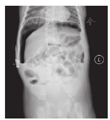

患儿发病前均无明确诱因,其临床表现为腹胀及呕吐(12例,44.44%)、腹胀(9例,33.33%)、反应差(3例,11.11%)及呼吸困难(3例,11.11%)。典型的新生儿胃穿孔立位腹部X线片表现为双侧膈下大量游离气体,内脏受压下移,严重者肝脏受压可呈半月形或马蹄形,胃泡变小甚至消失,出现横贯腹腔的大液气平面(图2)。